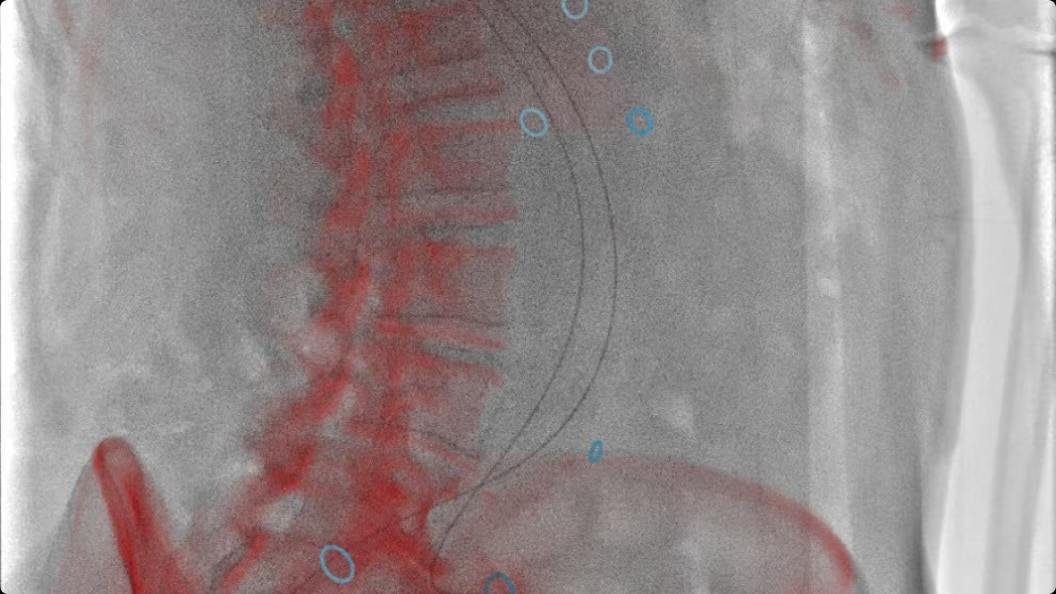

Enable flexible cone-beam computed tomography (CBCT) even on obese patients and adapt to constantly evolving procedures and techniques.

feature-3